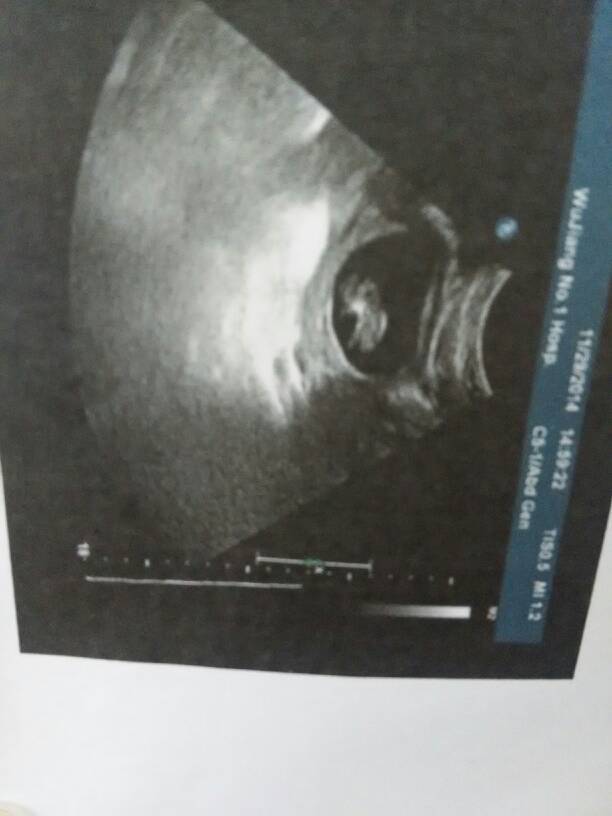

我今天去医院检查了,我的孕酮正常了,看看这是我家的宝宝 我今天去医院检查了,我的孕酮正常了,看看这是我家的宝宝 点击展开 忘记过去不再想过去 2014-11-29 15:58 为您推荐: 其他回答 一般的情况下,如果现在有胎心,胎芽的话,表示胎儿发育比较正常的,所以不要担心的。平时需要注意休息,加强营养,定期到医院进行复查的。 shenglongxiao 2014-11-29 21:30 祝宝妈好运哦!!! た海ご滩ルう 2014-11-29 16:35 !正常?。。 莹莹乘 2014-11-29 16:24 好孕!!!! 曹臭臭 2014-11-29 16:10 宝宝很健康 看不穿 2014-11-29 16:06 加载更多 相关问题 我今天去医院抽血检查,医生说,我的孕酮很低,正常的怀孕5周孕酮是2000而我的只有60!HCG正常 今天去医院检查,诊单列出孕酮数,还列着首孕三周,第二孕三周,这些是什么意思 今天去医院抽血检查怀孕没有,孕酮12 35 人绒毛膜促性腺激5503 00医生说刚受孕不